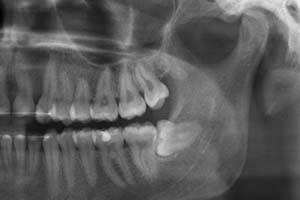

Die dritten großen Backenzähne (Molaren) nennen wir umgangssprachlich Weisheitszähne. Sie werden häufig erst mit einer Panoramaschichtaufnahme (PSA oder OPG) entdeckt und treten als letzte bleibende Zähne in die Mundhöhle ein. Sie unterscheiden sich teilweise gravierend in Anatomie, Form und Lage von anderen Backenzähnen.

Daher ist die operative Entfernung der Weisheitszähne einer der am häufigsten durchgeführten chirurgischen Eingriffe in der Zahnheilkunde. Diese muss nicht immer erfolgen, aber in vielen Fällen sprechen Gründe dafür, einen oder mehrere Weisheitszähne operativ zu entfernen. Massive Stellungsanomalien, bei denen die Weisheitszähne in falsche Richtungen wachsen, oder eine bereits erfolgte Zerstörung durch Karies können wie auch Durchbruchstörungen die Notwendigkeit einer Entfernung begründen. Oftmals ist vor einer geplanten kieferorthopädischen Behandlung die Entfernung zu diskutieren.